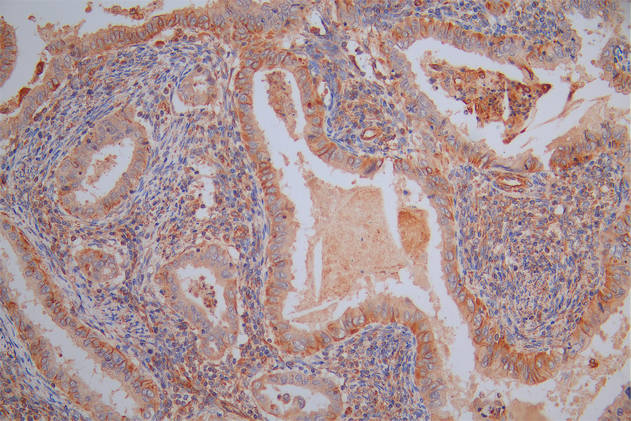

IHC image of CSB-PA896505DSR2HU diluted at 1:50 and staining in paraffin-embedded human colorectal cancer performed on a Leica BondTM system. After dewaxing and hydration, antigen retrieval was mediated by high pressure in a citrate buffer (pH 6.0). Section was blocked with 10% normal goat serum 30min at RT. Then primary antibody (1% BSA) was incubated at 4°C overnight. The primary is detected by a Goat anti-rabbit polymer IgG labeled by HRP and visualized using 0.05% DAB. Secondary antibody only control: uses 1% BSA instead of primary antibody